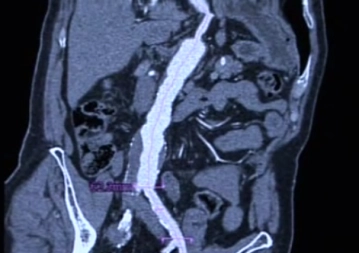

Assintomático: um aumento rápido no tamanho (> 4mm por ano) ou um diâmetro transverso de > 5 cm são critérios de decisão clínica para cirurgia; em mulheres, diâmetros menores já estão em risco de ruptura.

Sintomático: toda ruptura de aneurisma é uma situação de risco de vida e representa a indicação absoluta para cirurgia em todos os pacientes.

Nota: Mortalidade para intervenções de emergência: > 40 %, para intervenções eletivas: aprox. 3 – 5 %